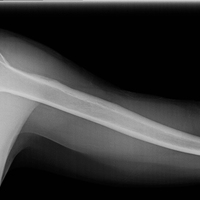

humerus

upper arm bone

radius

one of the bones found in the lower arm

ulna